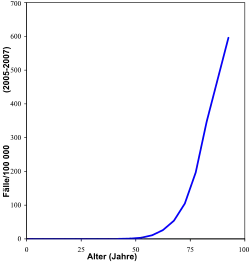

Das Prostatakarzinom ist in Deutschland die häufigste diagnostizierte Krebserkrankung des Mannes und steht nach dem Bronchialkarzinom an zweiter Stelle bei den krebsbedingten Todesursachen der Männer. Rund 26 Prozent aller bei Männern jährlich neu auftretenden Krebserkrankungen betreffen die Prostata. Das entspricht einer altersstandardisierten Inzidenzrate von etwa 99,1 auf 100.000 männliche Personen.[2] Nach einer aktuellen Statistik erkranken in Deutschland 2018 jährlich ca. 65.000 Männer neu an Prostatakrebs.[2] Die beobachtbare, vermeintlich starke Zunahme in den letzten Jahrzehnten ist eher auf verbesserte diagnostische Methoden und eine allgemein höhere Lebenserwartung zurückzuführen als auf eine tatsächliche Zunahme der Fallzahlen.

Die jährliche Mortalität (Gesamtzahl der Todesfälle) liegt um 15.000.[2] Nach einer Übersichtsstudie von 2015 stieg die Rate von „schlafendem“ (latentem) Prostatakrebs bei der Autopsie von Personen, die durch andere Ursachen gestorben waren, von 5 % in der Altersgruppe bis 30 Jahre auf 59 % in der Altersgruppe ab 80 Jahre.[3] Eine ähnliche Übersichtsstudie, ebenfalls von 2015, zeigte auf einer etwas abweichenden Datengrundlage denselben Trend.[4]